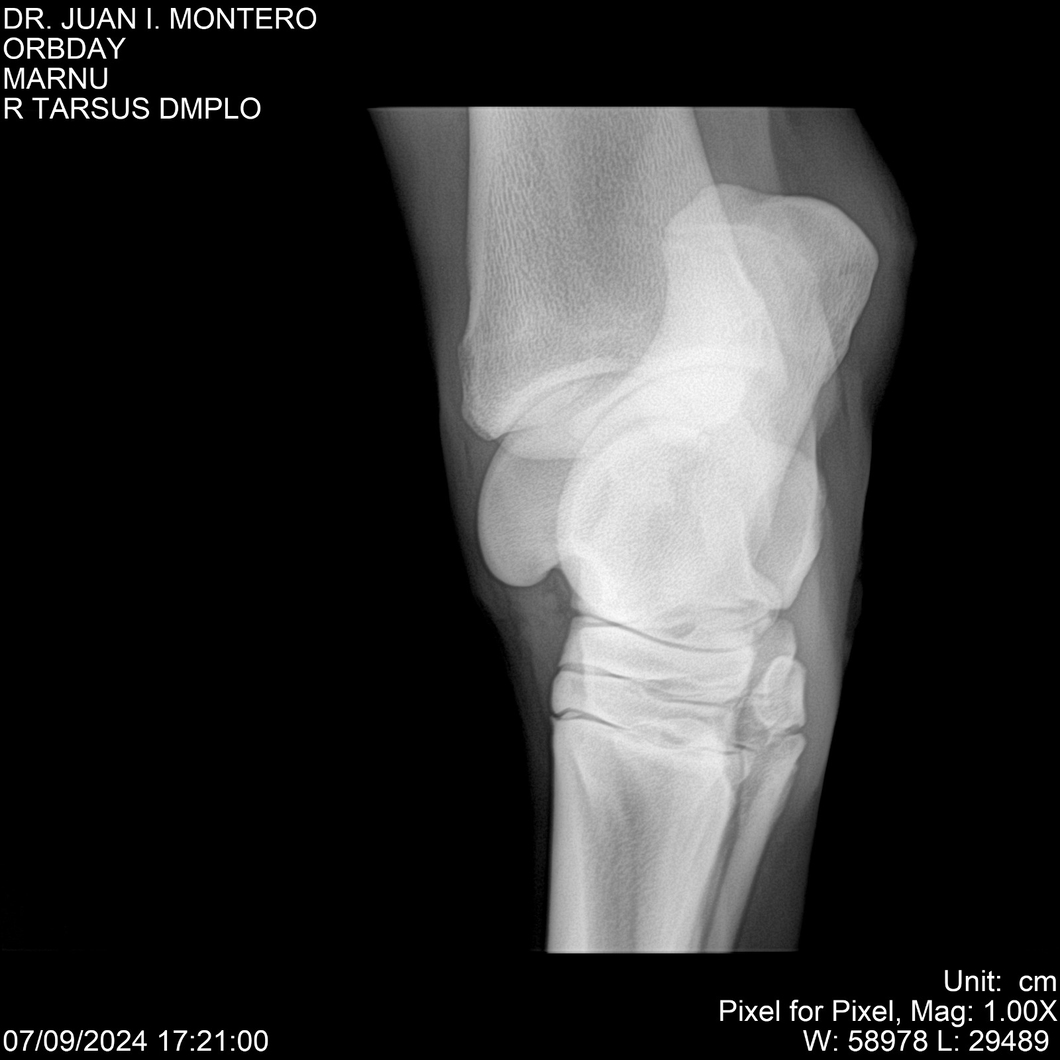

• Empresa: Abelenda N. R., Walter Hugo